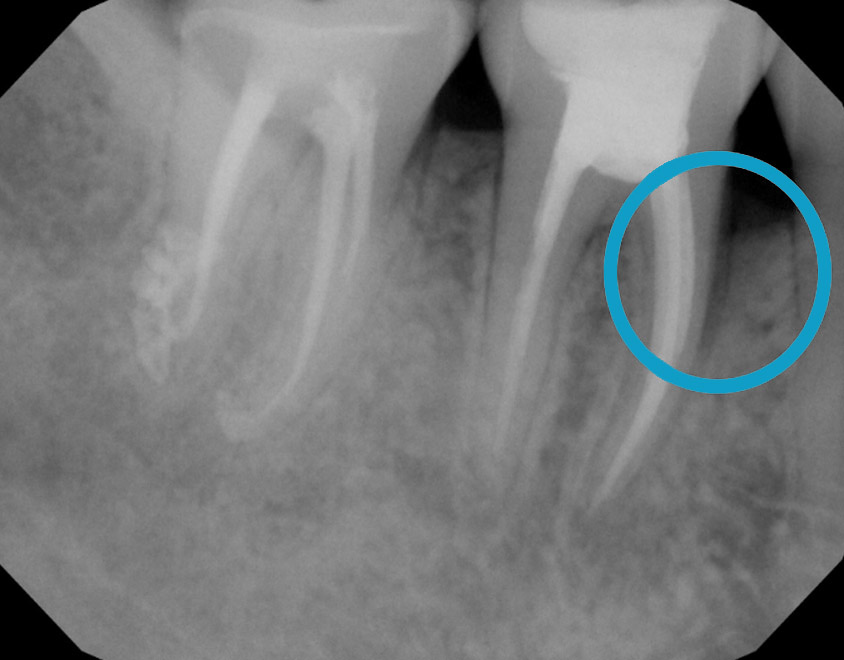

Treat severe gum disease and help the bone grow

One year after treatment, the bone has grown completely to a healthy level. It is all your own natural bone without the need for bone grafting.